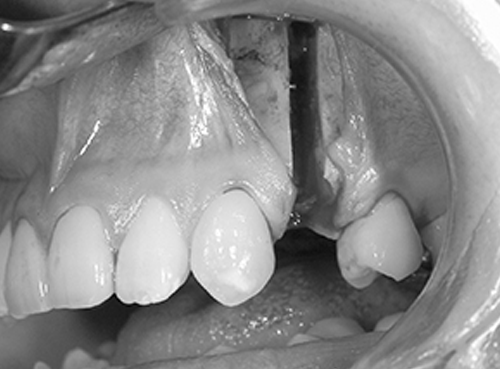

4. 切開をします

手術を始めます。

骨を削って、後ろに下げるために必要な範囲を切開します。

抜歯をした歯の部分に縦に1cmくらいの小さな切開をします。粘膜のみを切開し、他の組織を損傷しません。切開には15番メスや電気メスを使用します。切開面からガーゼを使って優しく手指ではがすと、骨の幕である骨膜が見えてきます。骨を切ったり、削ったりする部分だけを露出します。

5. 剥離します

剥離(口の中で骨が見える範囲)は、上は隣の歯の根っこまで、内側は小鼻の付近まで、お鼻の粘膜もお口の中から一部をはがしておくと、骨がきれいに切れて、手術後の出血が少なく、腫れも少なく、治りが早くなります。